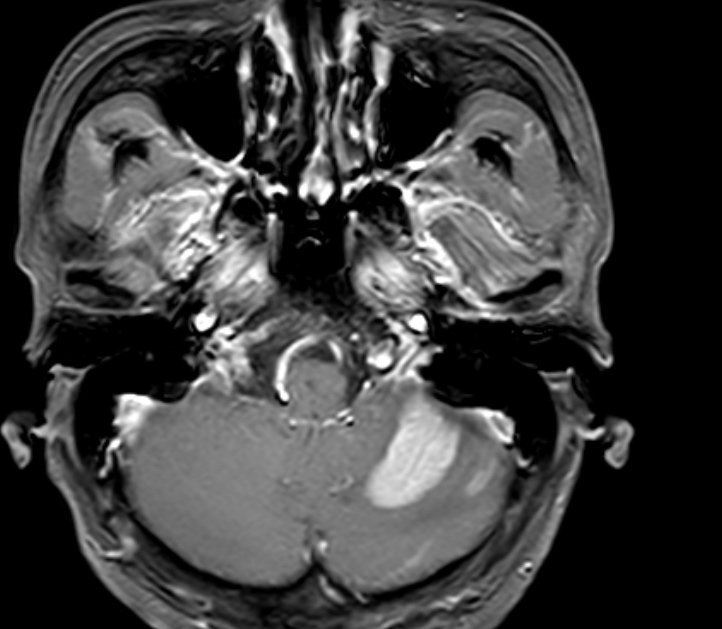

请教大家,小脑这个病灶用什么方法处理比较好,放疗还是伽玛刀

放疗的话可以考虑全脑,不适合刀,能看到脑膜强化

小脑是“单发或少数几个(如2-5个)”转移灶,且没有确诊或高度可疑的脑膜转移,医生的首选方案很可能是伽玛刀(或射波刀等其它立体定向放疗)。

如果脑内转移灶“非常多(如超过15个)”,强化或已“确诊脑膜转移”:

医生可能会推荐 全脑放疗,以期控制全脑范围的肿瘤细胞,包括脑膜上的病变。但需要权衡其对认知功能的损伤。

怎么说呢 就想把这个明显的病灶给处理掉那就伽马刀或者射波刀,现在描述脑膜,脊膜都有转移,后面治疗任重而道远的

有脑膜,更推荐全脑